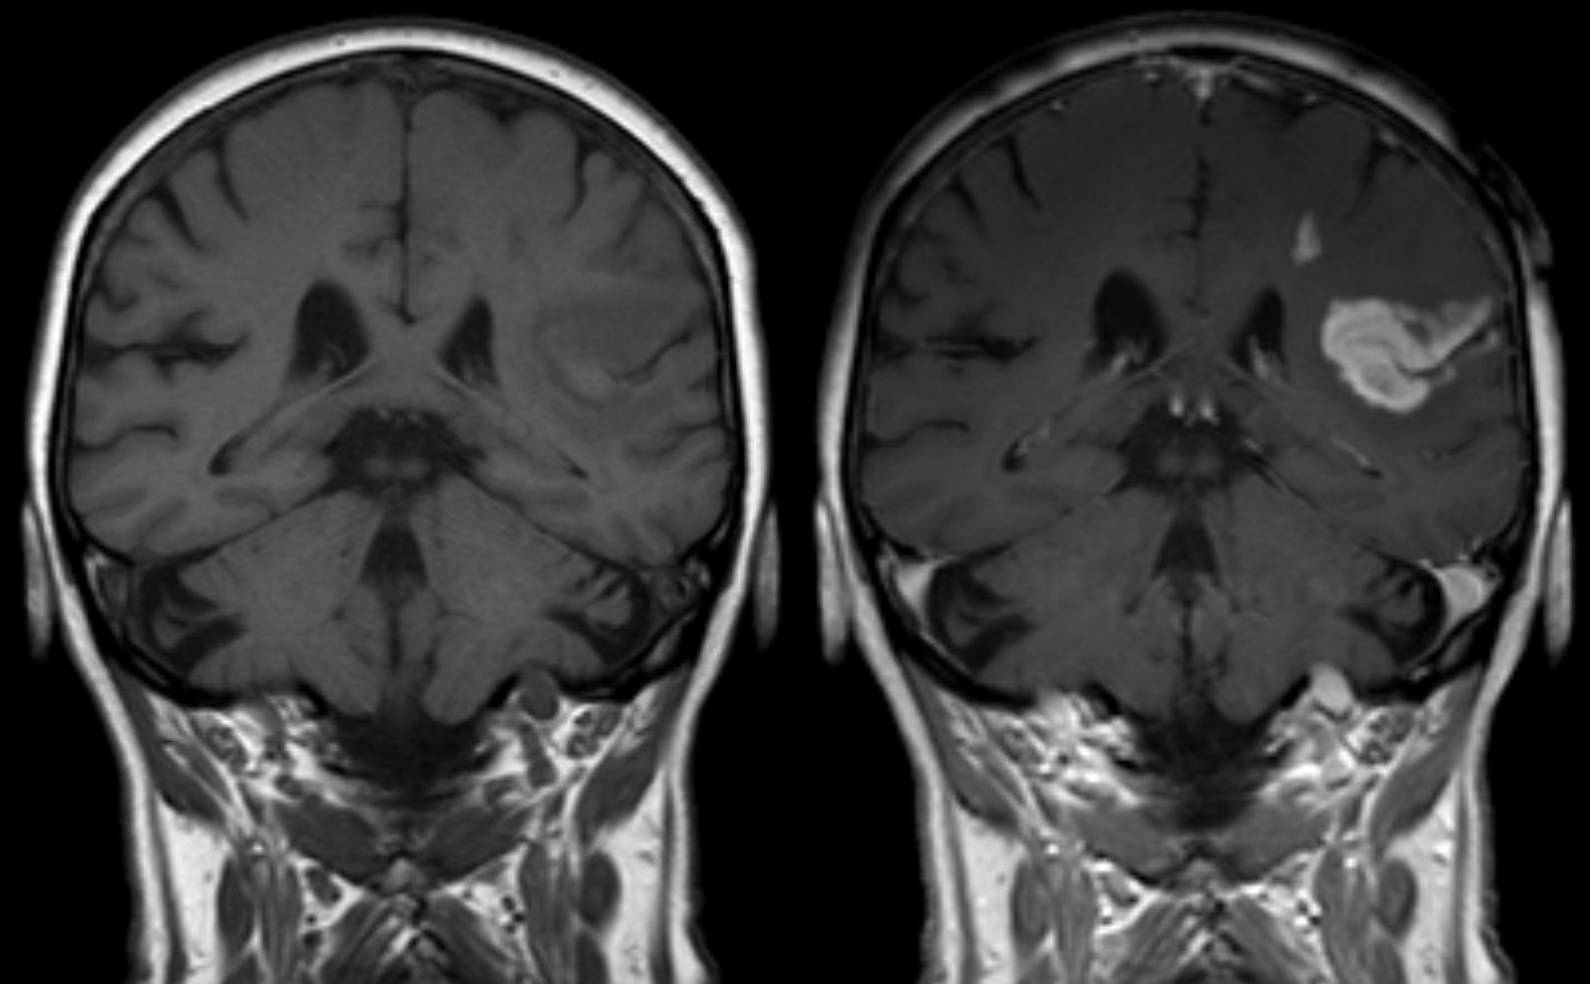

자기 공명 영상(MRI)에서 상자성 조영제는 주변 물 분자의 T1 이완 시간을 단축시켜 영상의 대비를 높이는 역할을 한다. 가장 널리 사용되는 것은 가돌리늄(Gd) 기반 조영제이다.[72]가돌리늄(Gd) 기반 조영제는 자기 공명 혈관 조영술(MRA)에서 혈관을 강조하거나, 혈액뇌관문이 손상된 뇌종양, 염증, 감염 등의 진단에 유용하다. 가돌리늄(III) 킬레이트는 친수성이기 때문에 정상적인 혈액뇌관문은 통과하지 못한다. 따라서 손상된 혈액뇌관문을 통해 가돌리늄(III)이 새어 나오는 부위를 강조하여 병변이나 종양을 발견하는 데 도움을 준다.